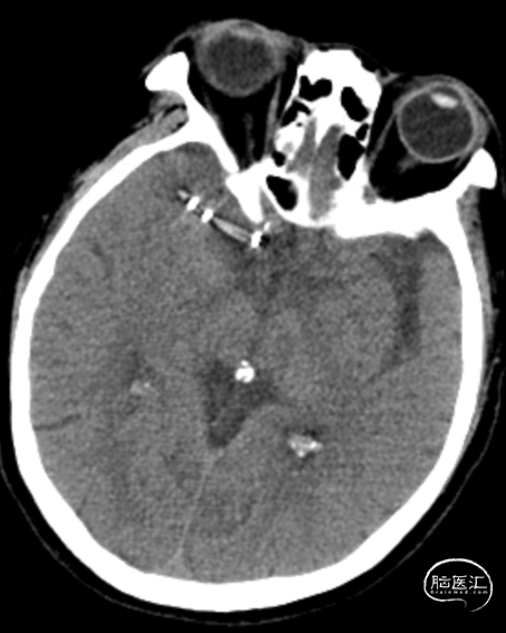

术前影像学检查

➢术前CTA

➢术前DSA

➢术前CTP

➢术前HMRI

➢术后次日CT

➢术后1周CTP